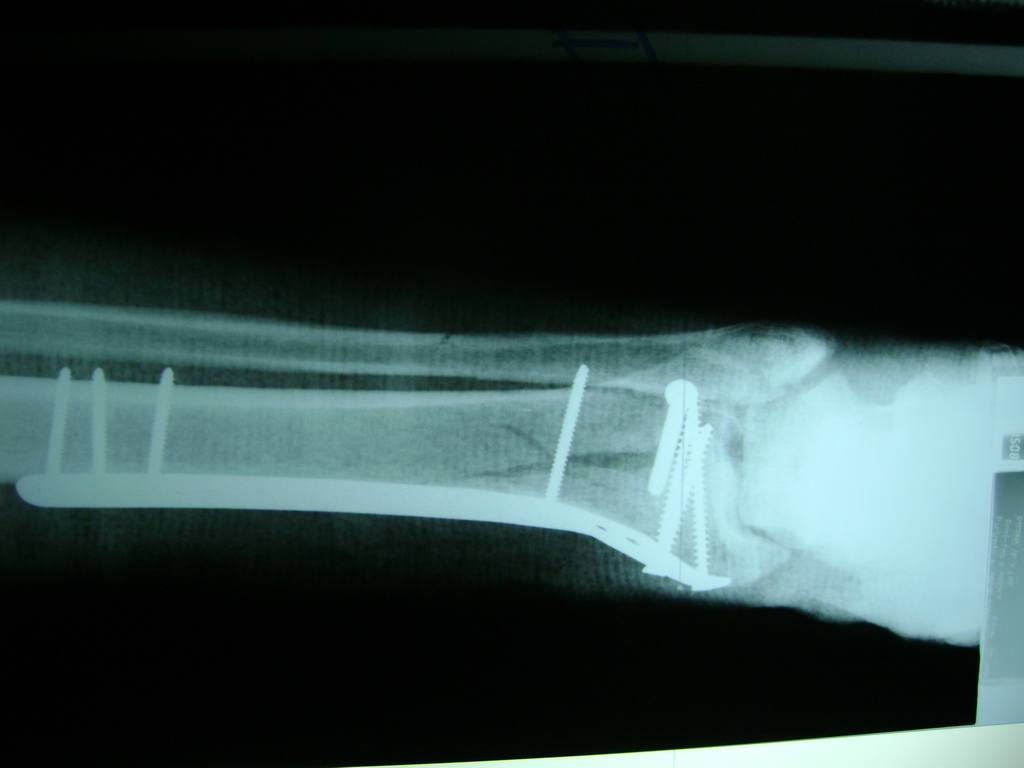

Calcaneo - Perone y Tibia

Aunque cada uno de estos huesos puede fracturarse por separado, normalmente la rotura es una lesión que se produce de forma conjunta

La mayor parte de las roturas implican a la parte proximal del hueso (parte del hueso próximo a la rodilla) o a la parte distal (parte del hueso cerca del tobillo).

Debido a la fina cobertura de piel que recubre la tibia y el peroné, las fracturas generalmente son abiertas, es decir, el hueso roto rasga la piel, atravesándola. Las fracturas de tibia y peroné generalmente se producen por un fuerte impacto o torsión.